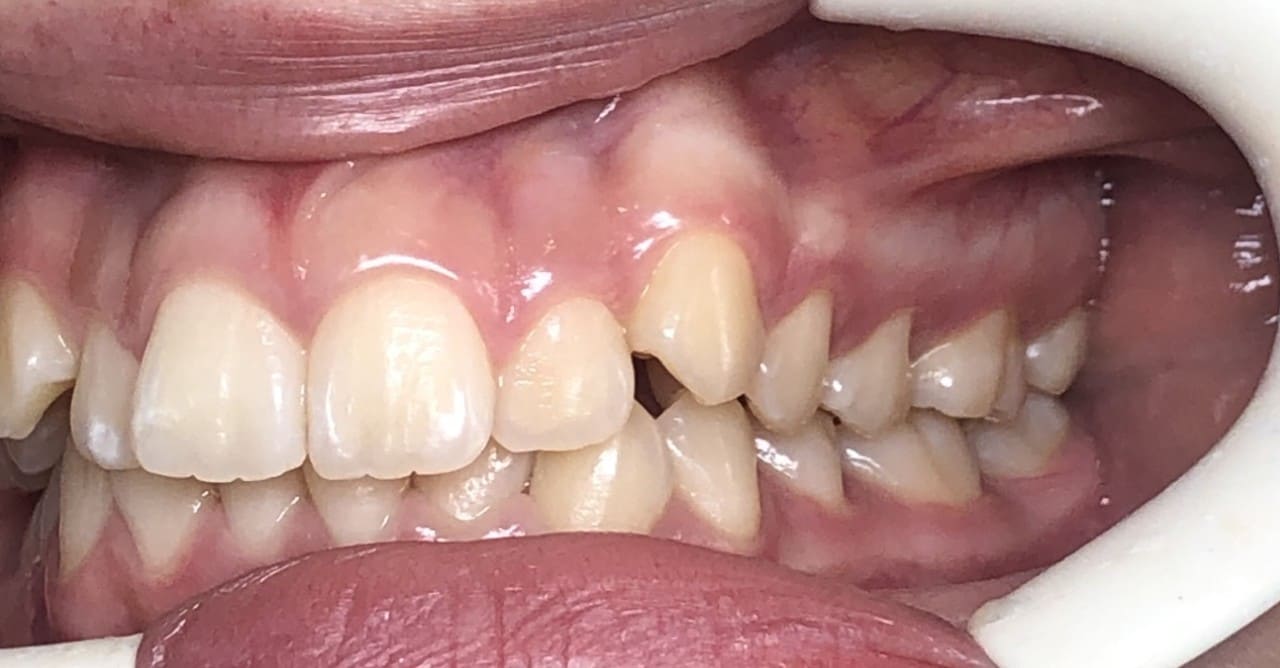

Initial

Final